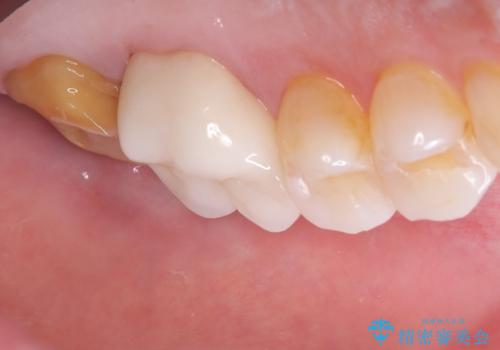

- 主訴:詰め物と歯の奥が側の境目に物がいつも溜まってしまう

保険適応のメタルインレーと歯質との間に不適合な箇所を認め、補綴物のやり替えでの治療となりました。インレーからクラウンへ補綴物の形態を変更し、素材は清掃性・適合性・審美性の点からセラミッククラウンでのやり替となりました。

レントゲン上にて、左上6番遠心にインレーと歯質の不適合を認めます。

健全歯質の残存量から、クラウンでのやり替えを提案しオールセラミッククラウン(スタンダード)でのやり替えとなりました。